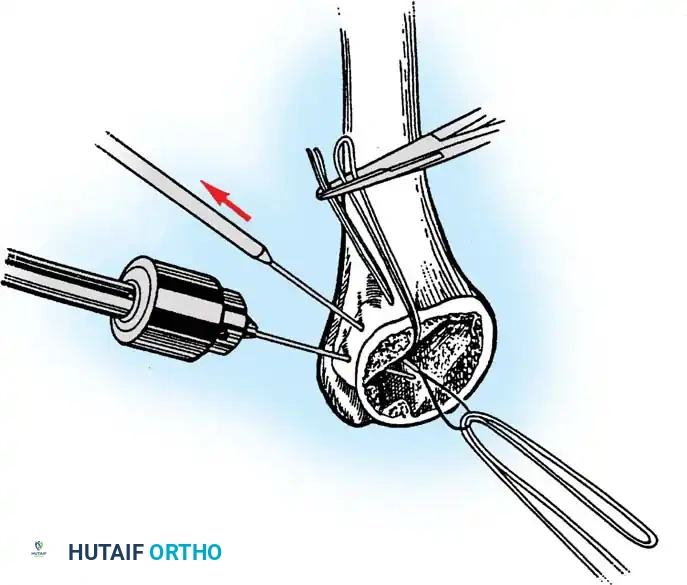

3. Canal Preparation and Implantation

The humeral and ulnar canals are sequentially broached.

- A cement restrictor is placed in both canals.

- Antibiotic-loaded polymethylmethacrylate (PMMA) bone cement is injected in a retrograde fashion.

- The components are inserted, and the articulation is linked using the manufacturer-specific locking pin mechanism.